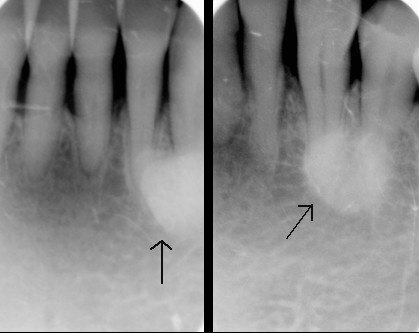

Tori and Exostosis: radiographs

appear as a radiopaque mass